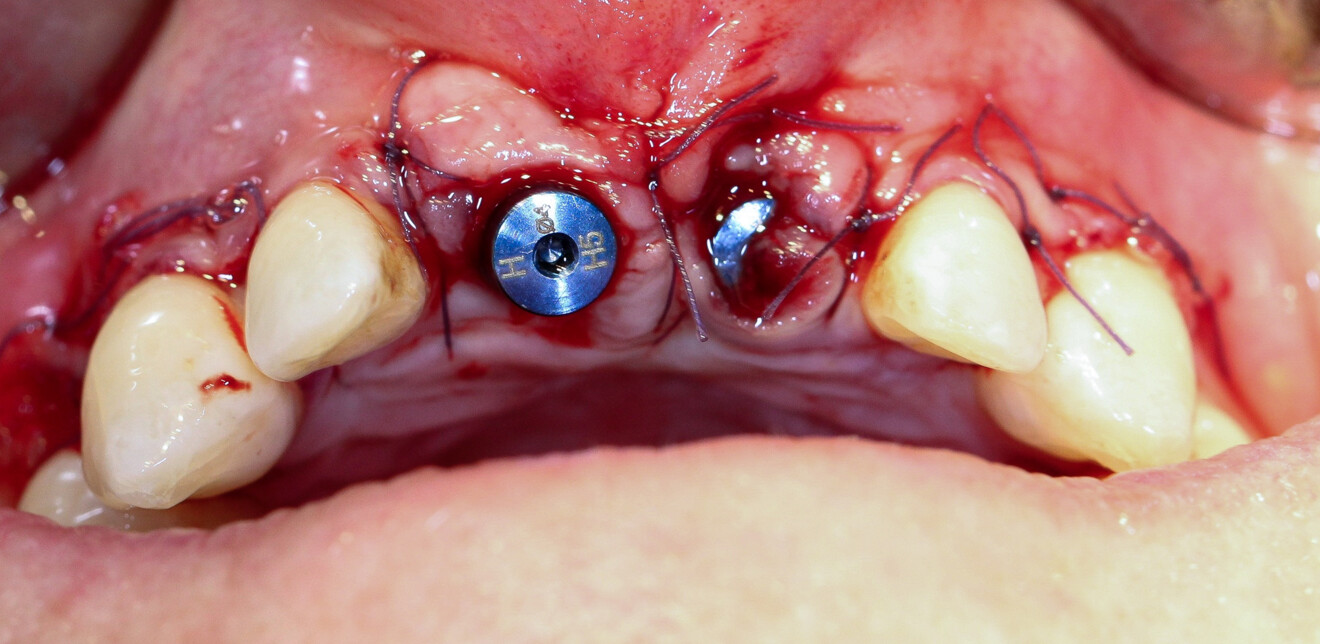

Fig. 8

Fig. 9

Fig. 10

À l’examen la patiente présente en vestibulaire, au niveau de 11 et 21, des pertes de substances importantes (osseuses et gingivales), particulièrement en 21 avec la destruction de l’intégralité de la paroi vestibulaire de la crète, et une perte totale d’ancrage de la racine, ainsi qu’un frein labial inséré haut sur la crête. On conserve néanmoins l’architecture des tissus mous avec la présence de papilles interdentaires et un volume osseux apical suffisant pour permettre l’ancrage des implants (Figs. 8–10). L’enjeux du traitement est de réaliser les extractions, de poser les implants, de reconstruire la crête osseuse, et de mettre en place des provisoires fixes sur les implants, en conservant l’architecture des tissus mous.